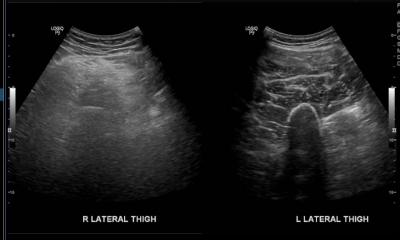

Figure 1: Ultrasound comparing the right and left thigh. Ultrasound showed muscles at lateral aspect of right thigh are heterogeneously hyperechoic. No collection seen at subcutaneous tissue or intramuscularly.